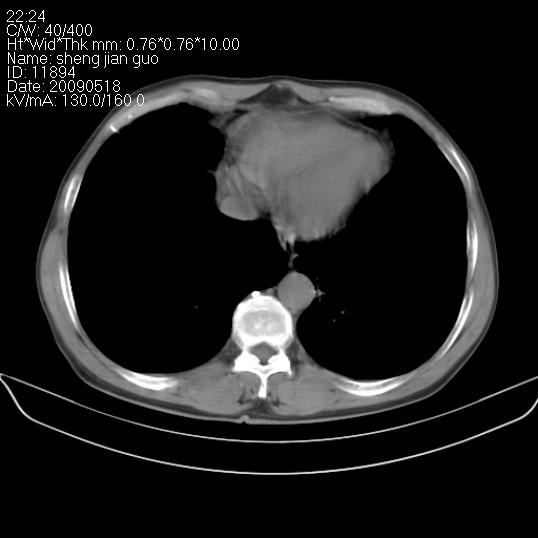

以下是引用zjzjr在2009-5-19 17:25:00的发言:[br]支持楼主考虑,另左肺下叶阻塞性炎症。

以下是引用zhao_bin2008在2009-5-19 17:48:00的发言:[br]支持左肺下叶周围型肺癌并阻塞性肺炎。

以下是引用zsl6918在2009-5-20 7:10:00的发言:[br]左侧中心型肺癌!